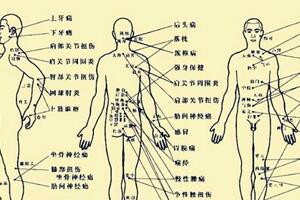

>>>>7. 按揉足三裡、陰陵泉和三陰交

足三裡、陰陵泉和三陰交都是很好的祛濕穴位,濕氣重的人平時可以多揉揉。

① 足三裡穴位於外膝眼下10釐米,用自己的掌心蓋住自己的膝蓋骨,五指朝下,中指盡處便是此穴。

② 屈膝,在脛骨內側髁的下方的凹陷中,就是陰陵泉穴。

在內踝尖上用自己的手指4指之上,按壓有一骨頭,三陰交穴位於脛骨後緣靠近骨邊凹陷處。